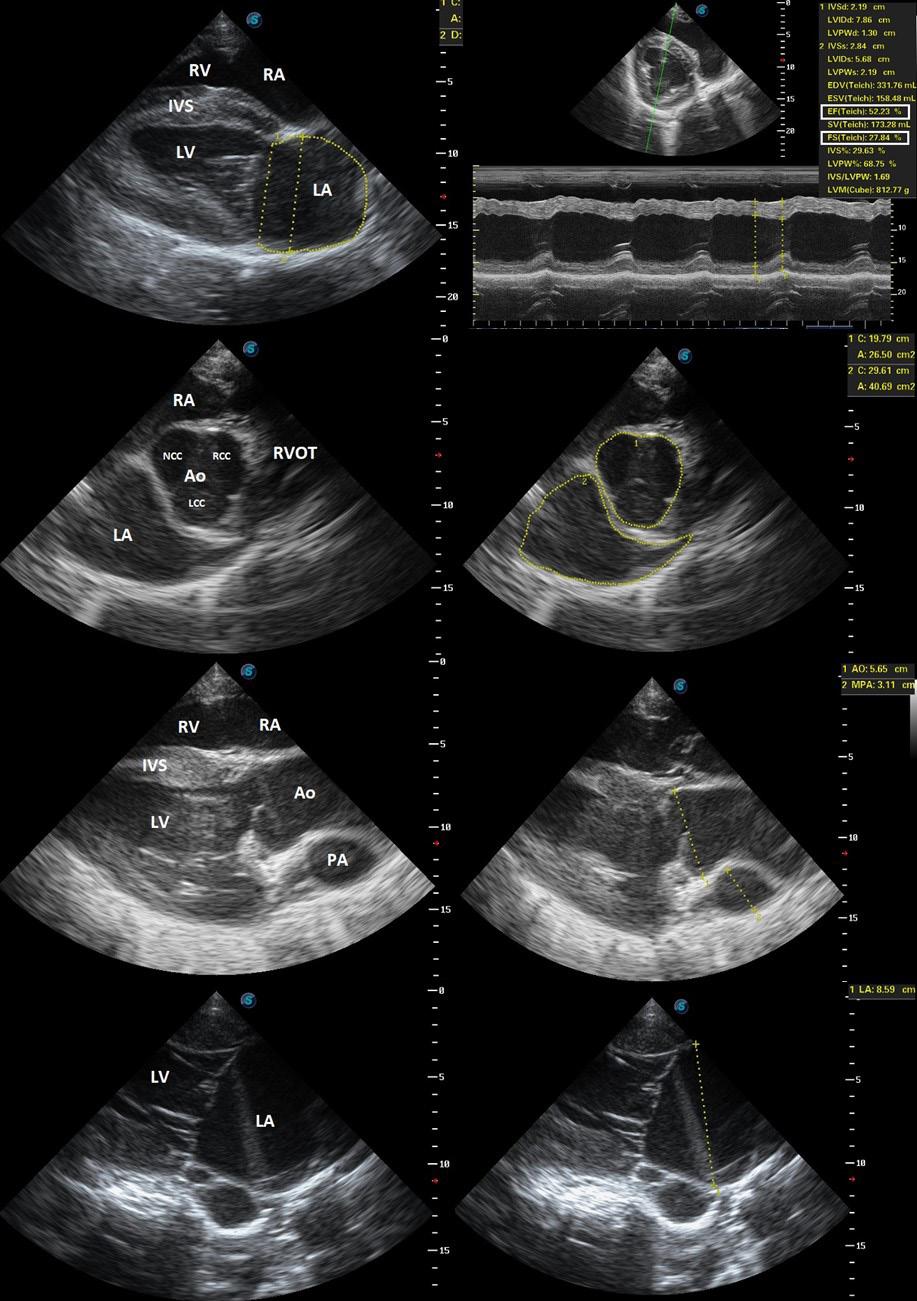

Echocardiographic evaluation of horses challenged with African horse sickness virus

African horse sickness (AHS) is an infectious, often fatal viral disease of equids with a severe impact on the equine industry in subSaharan Africa. Clinicopathological mechanisms are poorly understood, and there is limited information on the degree and type of cardiac involvement, especially during the course of the disease.

This study followed four horses experimentally infected with African horse sickness virus (AHSV) as part of a vaccine trial, to describe echocardiographic changes during the course of the disease. Echocardiography was performed once prior to infection, and daily from infection to humane euthanasia of each subject. Basic objective and subjective (eFoCUS) evaluations of all appropriate echocardiographic variables were performed.

An increase in diastolic myocardial thickness and a decrease in the size of the left cardiac chambers during diastole and systole were consistent findings on the last day of evaluation of each subject and suggestive of hypovolaemia. The cause of the suspected hypovolaemia was not investigated, but increased vascular permeability causing third space volume loss was considered the most likely cause, as this is associated with the disease process. During the eFoCUS evaluation substantial and perfect interobserver agreements were found for an

increase in myocardial thickness and diminution of the left ventricle, respectively, suggesting that these variables could be used to subjectively evaluate cardiovascular status in clinical cases in an emergency setting. In addition, perfect interobserver agreement for impaired diastolic function, and almost perfect agreement for

pericardial effusion, was found during the eFoCUS evaluation of the final data sets for each subject. Further studies are needed to confirm the presence, quantify the severity, identify the cause and significance of these findings in both clinical and experimental environments.